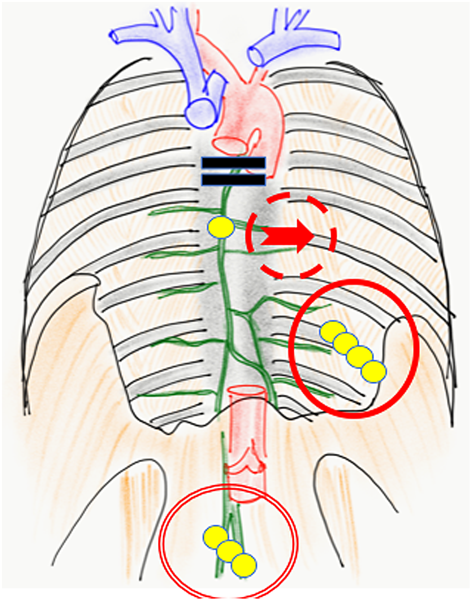

Fig. 1 The protocol of treatment indications

The indications of lipiodol lymphangiography and lymphatic venous anastomosis.

This study involved 12 infants who were under observation for ≥6 months after surgery from April 2014. All the patients had undergone medical treatment for ≥4 weeks with limited effect and therefore required surgical treatment. The patients were aged 30 days to 2 years (mean age, 9 months; median age, 8 months) and included 6 males and 6 females, 5 of whom had underlying diseases other than cardiovascular diseases (3 with trisomy 21, 1 with refractory hydrocephaly, and 1 with Noonan syndrome). The patients had severe congenital cardiac diseases such as common ventricle, tetralogy of Fallot (TOF) with pulmonary atresia, and Ebstein anomaly (Table 1). Lymph flow testing and treatment included lymphography (LG; indocyanine green [ICG], Lipiodol; detailed below) and lymphaticovenular anastomosis (LVA). In the patients without a right-to-left shunt, LG was performed, and LVA was indicated in patients with a right-to-left shunt, suspected congenital diseases, and edema (Fig. 1). All the surgeries were performed under general anesthesia (total intravenous anesthesia [TIVA]). ICG fluorescence imaging, LG, and LVA were performed with the approval of the institutional ethics committees of our hospital.